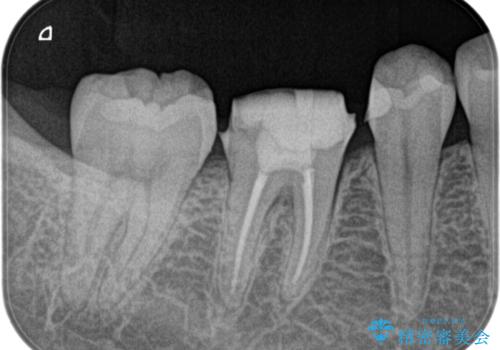

奥歯の根管治療~オールセラミッククラウン